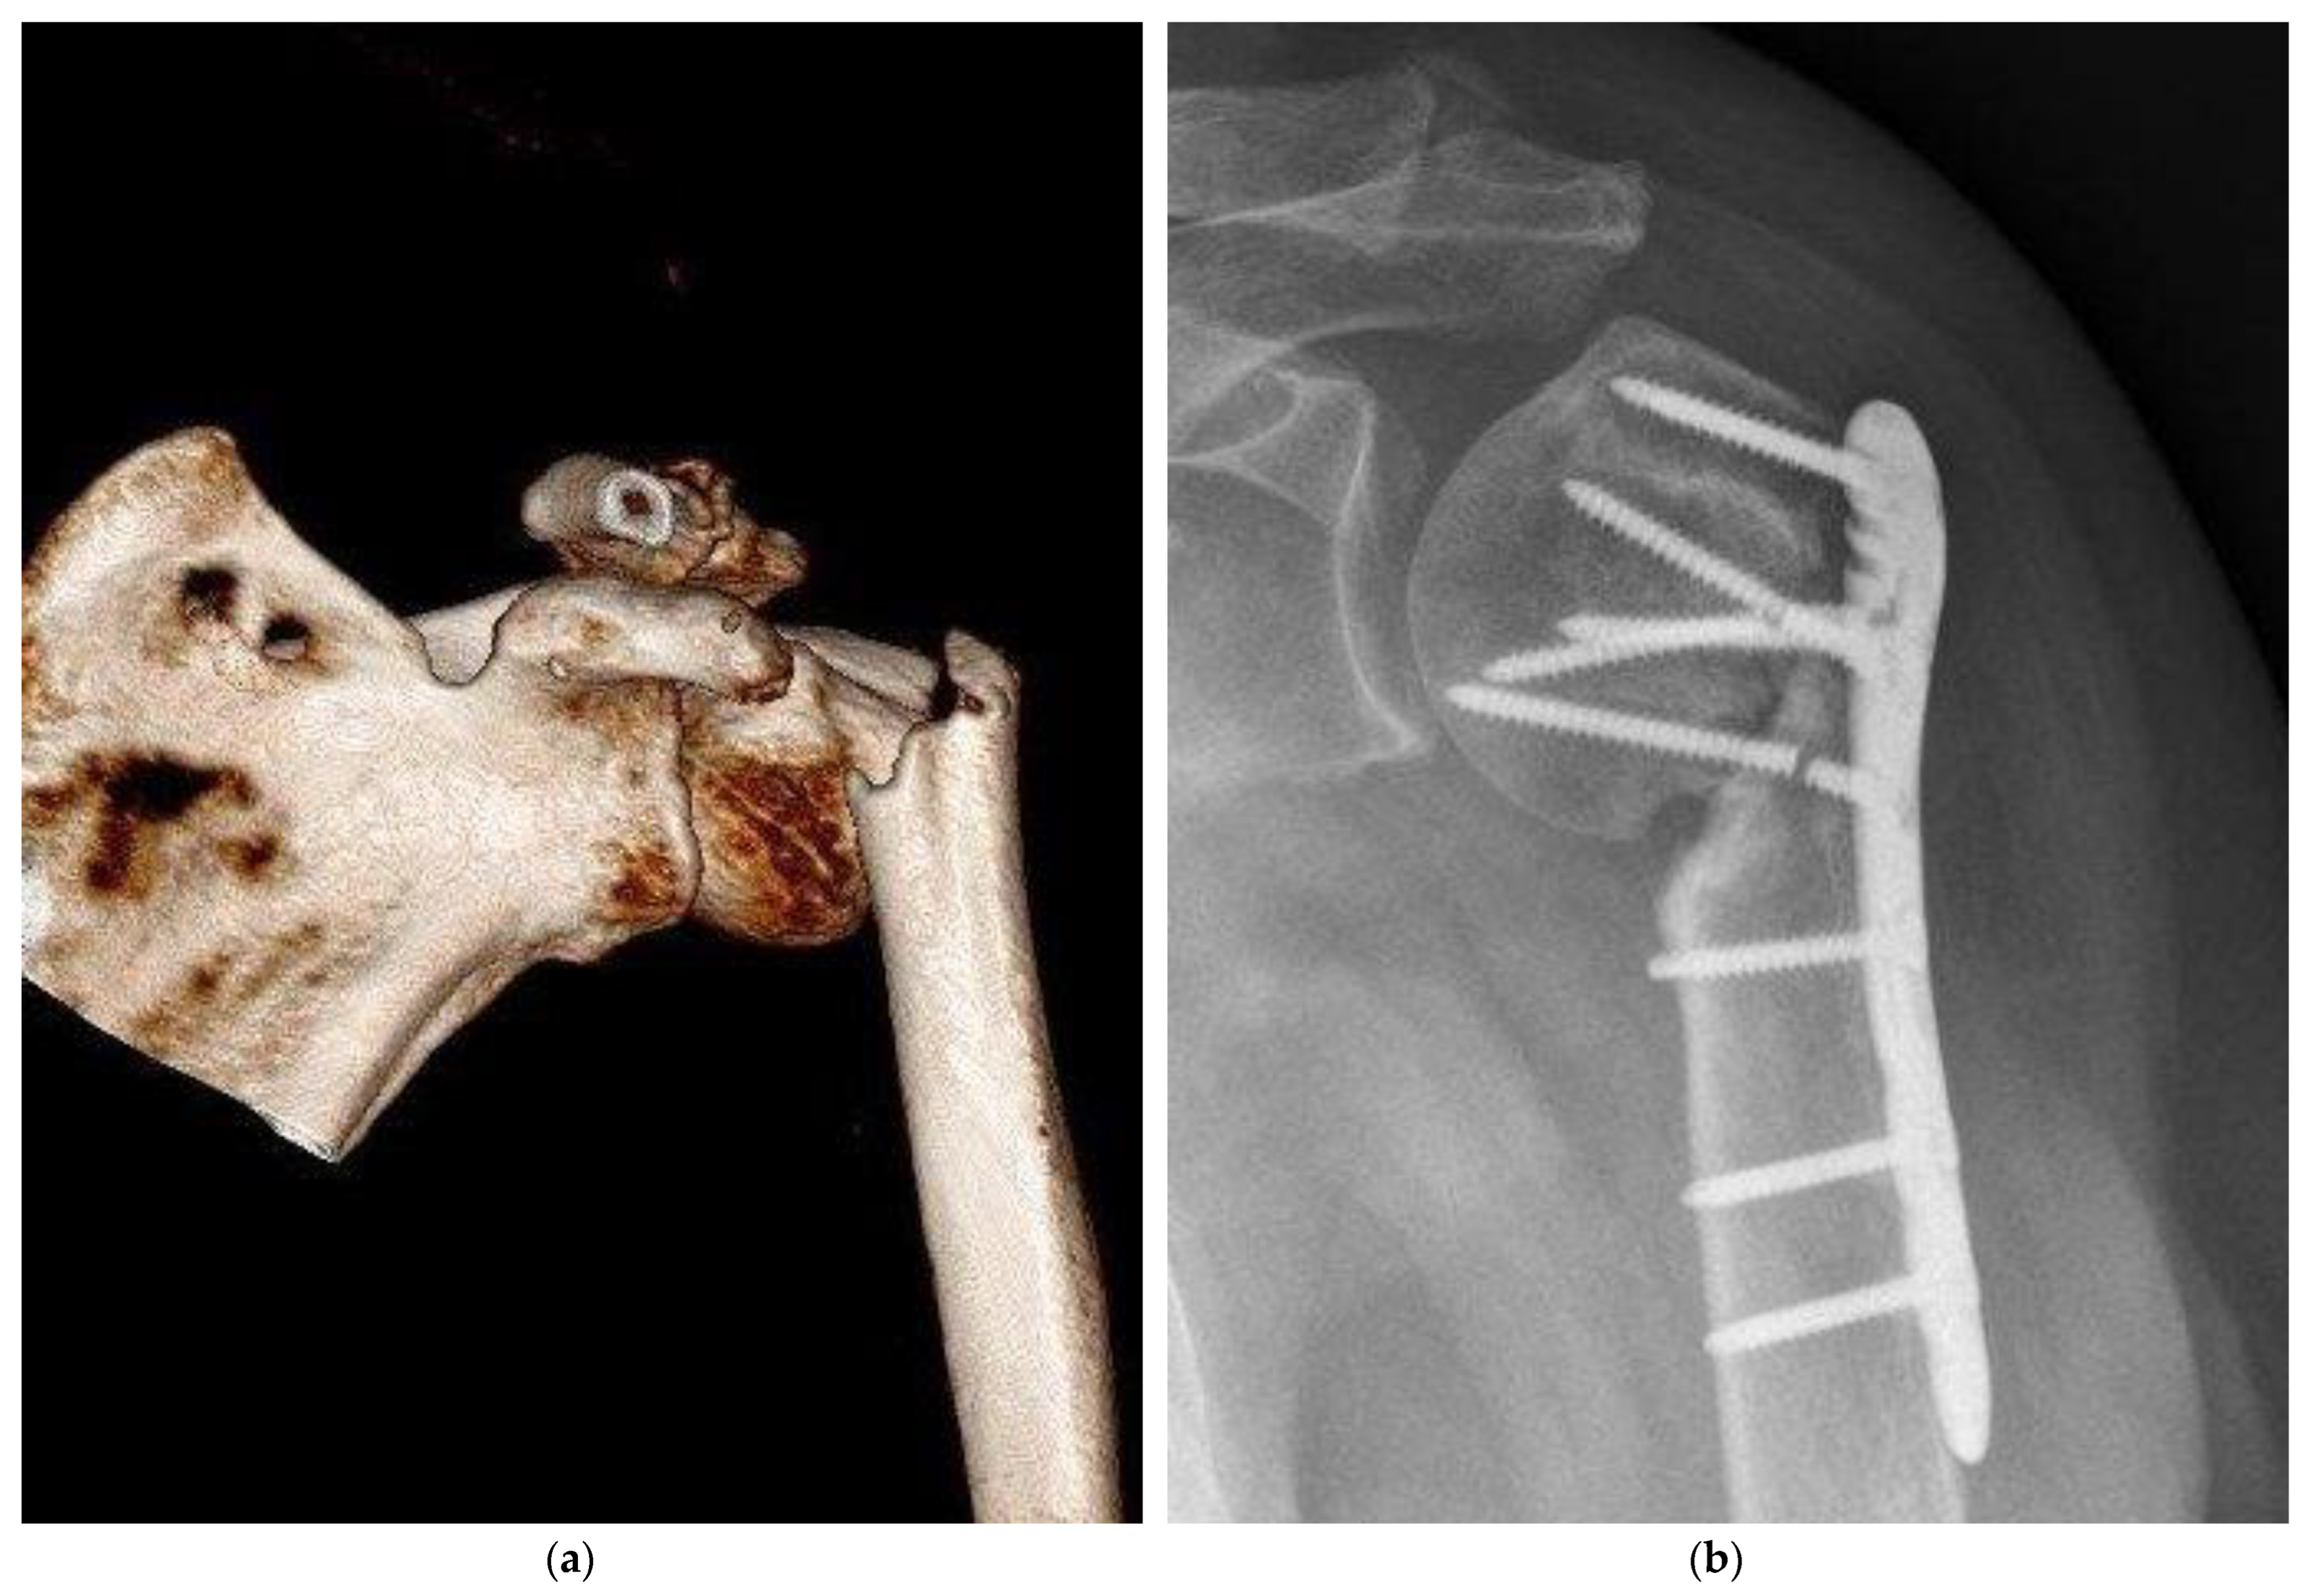

Figure 3. Severe complication, pseudarthrosis, resulting from a proximal humeral fracture, resulted by empty defect treatment. (a) Preoperative 3D CT reconstruction showed a sub-capital humeral fracture; (b) post-surgical care radiograph examination demonstrated an atrophic nonunion. Furthermore, two screws of the humeral head were broken.